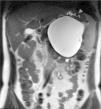

Mujer de 36 años con tumoración quística pancreática y trombopenia